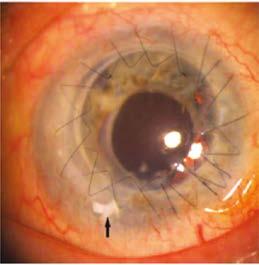

A la exploración oftalmológica presentó agudeza visual mejor corregida (AVMC) de 20/20 en ojo derecho (OD) y 20/30 en OI, presión intraocular en 16 mmHg ambos ojos (AO), motilidad ocular y reflejos pupilares conservados. A la biomicroscopía (BMC) se constató en OI un crecimiento intraepitelial (Imagen 1) y fondo de ojos (FO) AO normal.

Se le realizó una tomografía de coherencia óptica de segmento anterior (OCT SA), donde se visualizan pequeñas áreas de hiperreflectividad compatible con los nidos epiteliales, además, se puede evidenciar zonas de adelgazamiento del flap corneal desde la periferia hacia el centro. A su vez, se observa el sector de amputación del flap por donde se produjo el

Imagen 1. Fotografía de la BMC donde se observa el crecimiento intraepitelial. A, obtenida con corte de luz blanca. B, tomada con luz azul observándose la tinción por pooling por irregularidad en el flap. Imagen 2. OCT SA OI donde se aprecian los nidos epiteliales hiperreflectivos.

crecimiento intraepitelial. (Imagen 2). La topografía presenta irregularidad en los anillos de plácido en OI concordante con la irregularidad epitelial. Se informa alterado el resultado del índice de dispersión objetiva (“Objective Scatter Index” u OSI) en el HD Analyzer, es un parámetro que brinda información respecto a la dispersión de la luz y a la calidad visual dependiendo de la opacificación de medios y la calidad de la lágrima.